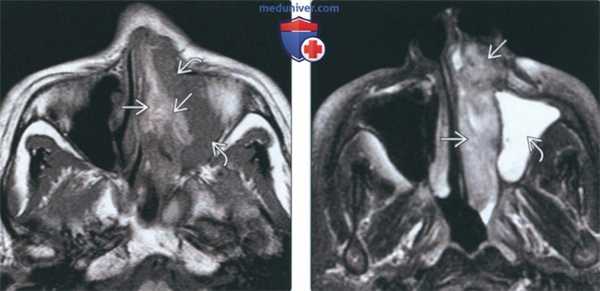

(Слева) На аксиальной МРТ (Т1 ВИ) определяется объемное образование в полости носа слева, распроараняющееся в верхнечелюстную пазуху. Опухоль неоднородна за счет учааков укорочения Т1 и промежуточного сигнала. Укорочение Т1 на бесконтрастных изображениях может означать наличие меланина.

(Справа) На аксиальной МРТ (Т2 ВИ FS) в полости носа слева визуализируется меланома с бугристыми краями. Меланома несколько гипоинтенсивна и легко отличима от гиперинтенсивного «запертого» секрета в левой верхнечелюстной пазухе.